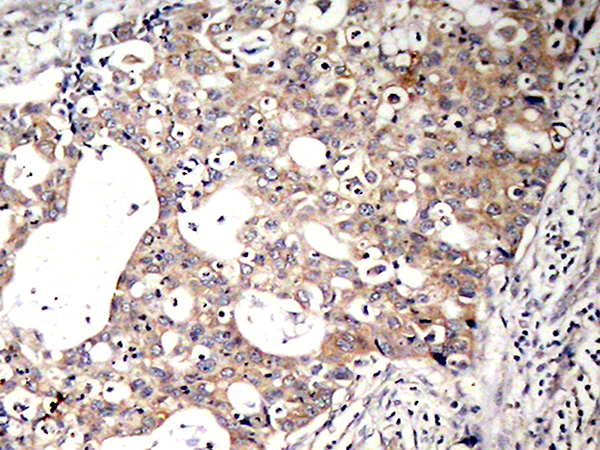

IHC positive control:

Human breast carcinoma

IHC Recommend dilution:

50-100